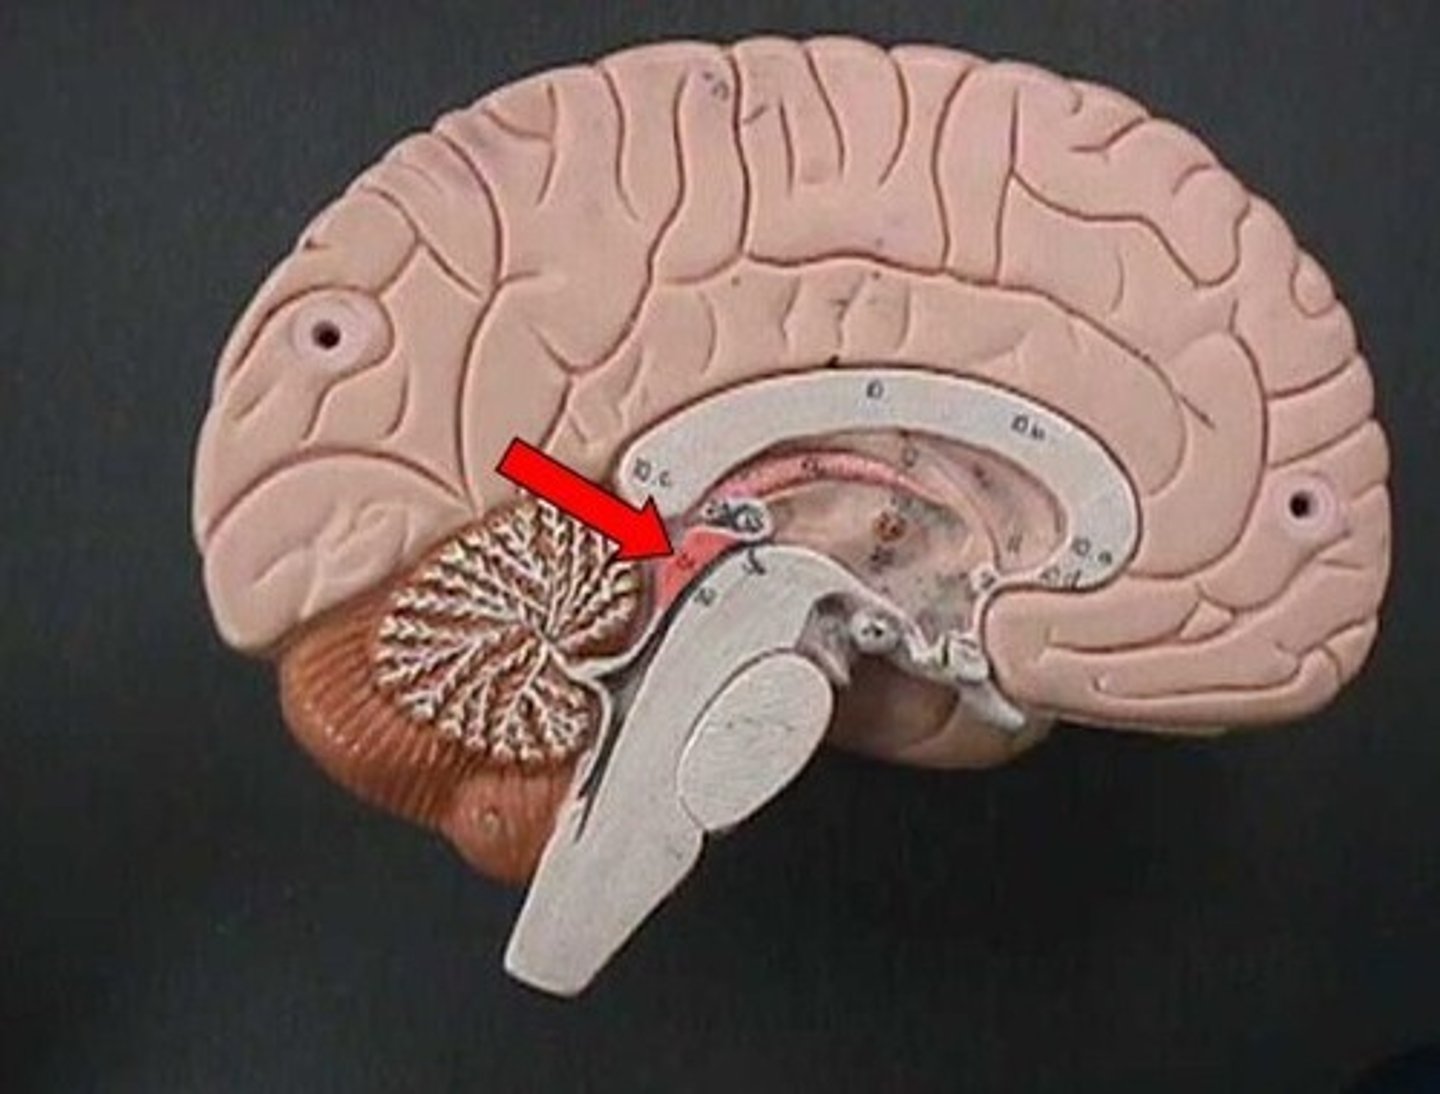

cerebellum

midbrain

pons

medulla oblongata

4th ventricle

cerebral aqueduct